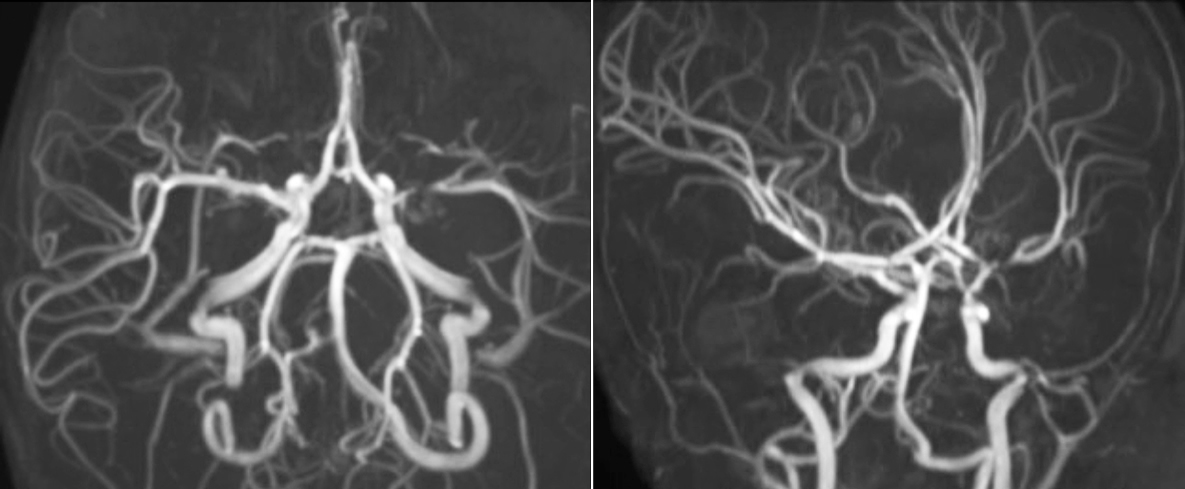

The value of susceptibility weighted imaging in visualizing brain injury is well documented. The Philips multi-echo SWIp technique provides fast susceptibility weighted imaging with enhanced susceptibility contrast and high resolution.

“Pediatric imaging is not without its challenges,” Dr. Miller says. “Since our patients are often very small, we need very high-resolution imaging. In cases of brain injury, we need to obtain information quickly so the treating clinicians can make decisions on care. We rely on high resolution and robust imaging capabilities, and SWIp provides that.”

“SWIp helps us identify blood or blood products, calcification, and diseases that affect the vascular system,” says Dr. Miller. “In children with traumatic brain injuries, it highlights areas that are injured, better than some of the previous techniques that we were using. These children often have micro-injuries that cause small amounts of blood or tissue damage. Adding SWIp helps us to better characterize the extent and nature of the injury. Having characterized an injury to the extent of what’s possible supports our diagnostic confidence.”

“I would definitely recommend other users to implement SWIp. We initially added the SWIp sequence following a lot of support for its utility in the literature. Then we directly compared SWIp to the 2D gradient echo sequences that we were using. After a good amount of clinical experience in seeing its benefits, we were confident to replace the old sequences with SWIp. It gives us a better assessment of the physiological processes of the brain that were less apparent on our previous imaging sequences,” says Dr. Miller. “SWIp is now a routine sequence for imaging traumatic brain injury patients at PCH, and it’s episodically added for patients who have intracranial vascular abnormalities.”

“I believe SWIp is rapidly becoming the standard in imaging traumatic brain injury, because of its high sensitivity to venous blood products. SWIp may even help attract patients; our neurosurgeons often ask to have the patients imaged on our scanners with highly sensitive techniques like SWIp. There’s also a growing application of SWI sequences in other vascular abnormalities because of the possibilities around physiological assessment of the brain than just a standard structural imaging.”